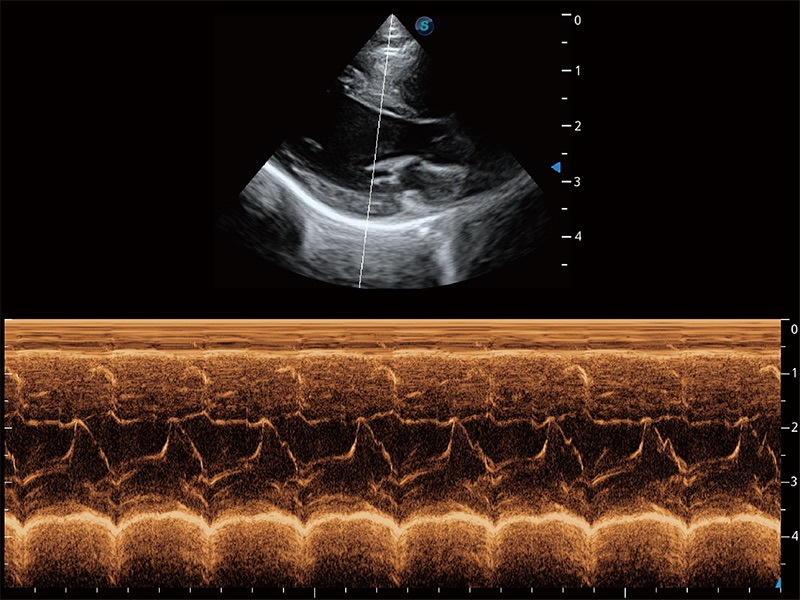

通过360度任意调节3条M型取样线,在同一心动周期上观察心脏不同位置的运动曲线,得到准确的心功能测量数据,有效评估心肌运动及左心室功能。